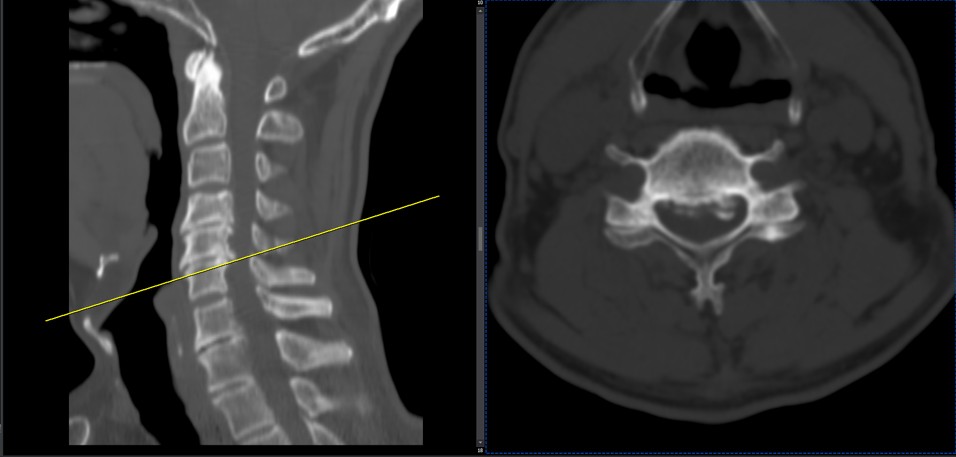

41 years old man presented to my clinic in October 2023 with acute and sever R neck pain with radicular pain to his R upper extremity along C6 dematom since 2 weeks ago. Examination didn’t show any upper motor signs. Was suggested urgent surgery

I ordered EMG/ NCV : showed mild R C6, C7 irritation without any active axonal loss

In his MRI was reported R. para R. IVF Massive extrusion. I decided to control his pain and manage this patient with reevaluation of patient every other session. For 5 sessions i just used acupuncture and laser and IFC and mild adjustments to his R. T3-T7 and mild arthosteem to above and below involved segment. Cervical adjustment considered contraindicated for this patient. From session 6th- 8th i started to use mild/gentle cervical decompression. He used soft cervical collar all the time. His pain decreased by 80 percent

I gave him cervical traction pump to be used 3-5 times per day at home for the next 3 months and i released the patient. He was evaluated every week once for one month and after that every 2 weeks. After 3 month I repeated MRI. Size of the herniated disc was reduced greater than 50 percent. Asked him to do another mri in 6 months

In general: Precise selection of the patients, examination,diagnosis, plan of management, reevaluation and treatment can be done by doctors of chiropractic for the patients with spinal disc herniation and stenosis Moreover giving reasonable time to these kind of patients under direct supervision by their chiropractic doctors can prevent unnecessary surgery. Proper selection of these kind of patients is another important fact that can be done precisely by chiropractors.

MRIs before and after proper management of this patient: